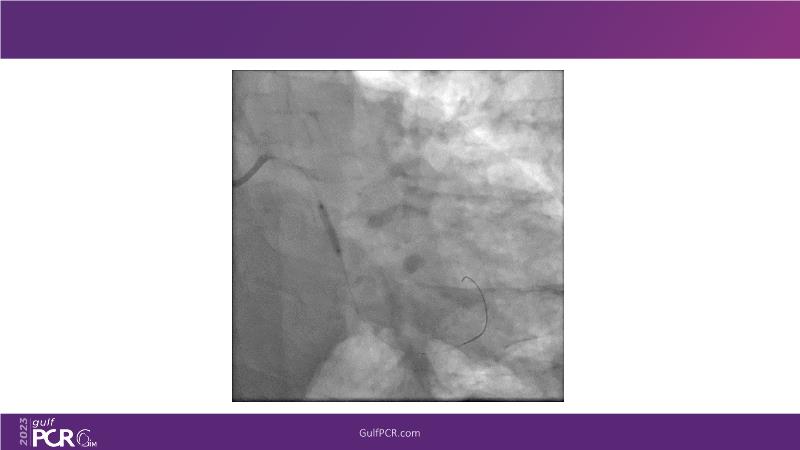

This session is a valuable resource for grasping innovative strategies in handling bifurcation and extended diffuse lesions through dedicated stenting solutions. Explore insights into the advanced Myval next-generation THV technology, unveiling its distinctive features, procedural advantages, and clinical outcomes across a diverse patient pool. Gain understanding into the CorAlign technique, ensuring accurate commissural and coronary alignment while maintaining coronary access. Additionally, delve into the techniques for precise sizing, positioning, and deploying of Myval THV.

- To understand novel tools and techniques for effective management of bifurcation lesions and long diffused lesions using dedicated stenting solutions